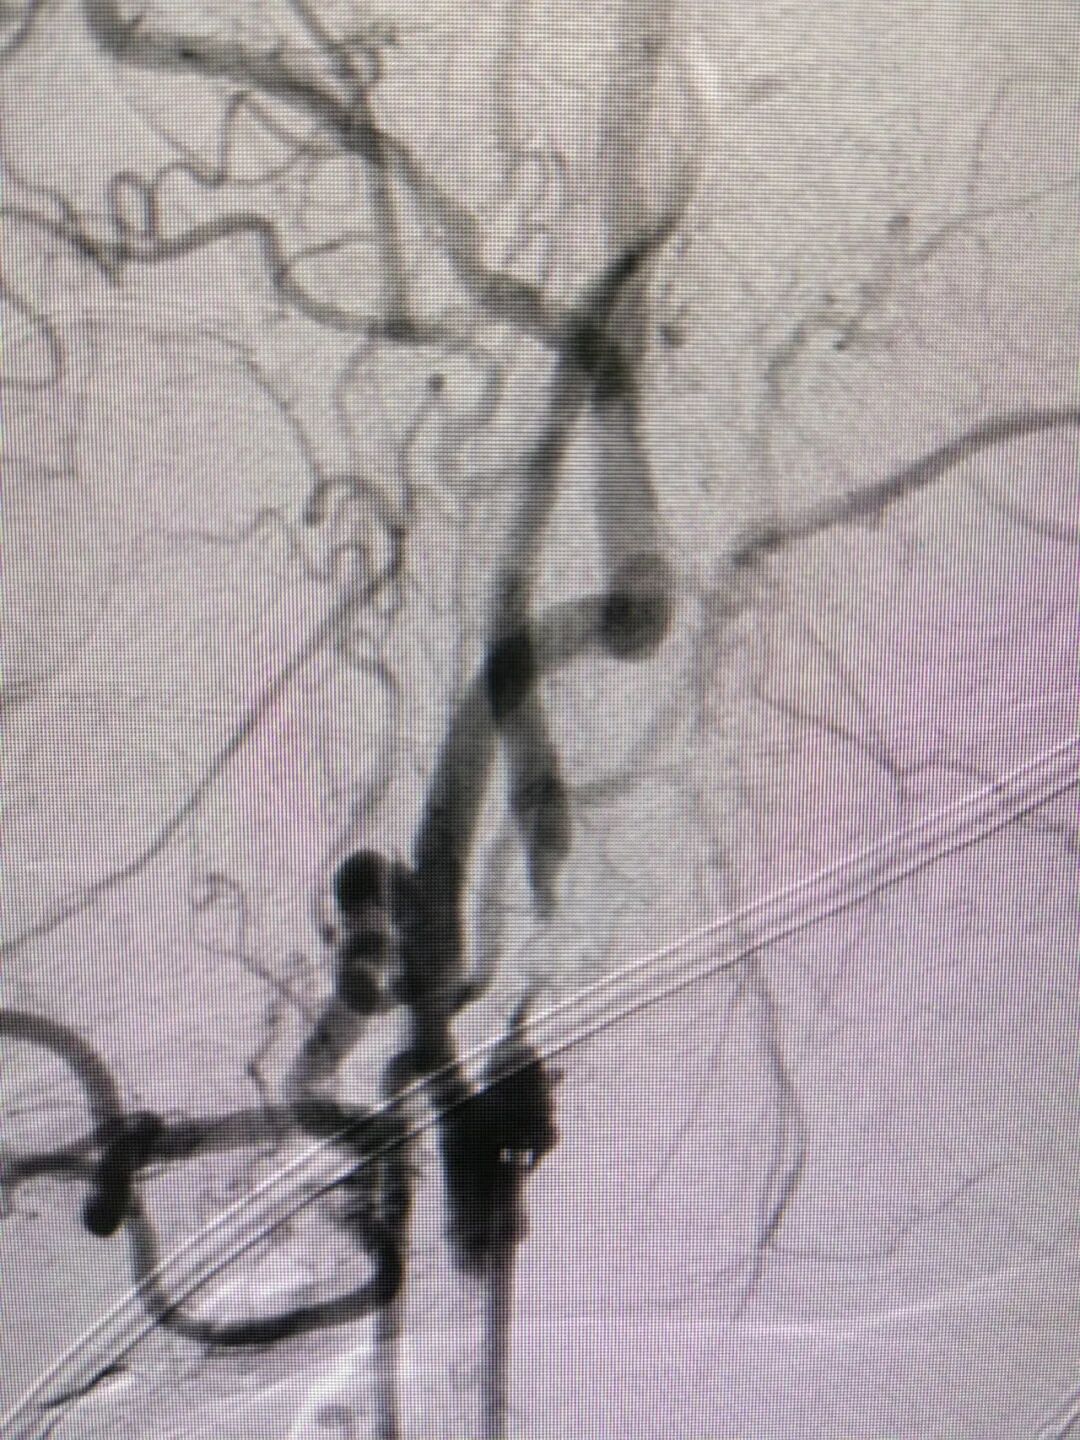

手术过程

经右侧桡动脉穿刺置入7F 薄壁鞘,畅医达 Calvada 5F 内腔0.072'' 导管鞘同轴125cm 5F 西蒙Ⅱ导管,在0.035'' 导丝引导下顺利到达右侧颈总动脉远端,小球囊预扩后,送入5mm 保护伞,4.0mm×30mm 球囊扩张后置入7mm×40mm 颈动脉支架。

术后影像

术后患者神志清楚,左侧肢体肌力4级,NIHSS评分:3分。